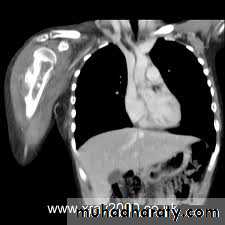

And the extension in to the medullary canal (skipped lesion).CT and chest radiograph is mandatory for preoperative staging

The skeleton is one of the commonest sites of secondary cancer;in patients over 50 years bone metastases are seen more frequently than all primary malignant bone tumours together.

Most skeletal deposits are osteolytic and appear as rarified areas in the medullaor

produce a moth-eaten appearance in the cortex.

sometimes there is marked bone destruction, with or without a pathological fracture.

Radioscintigraphy

Bone scans with 99mTc-MDP are themost sensitive method of detecting ‘silent’ metastatic

deposits in bone; areas of increased activity are selected for x-ray examination.